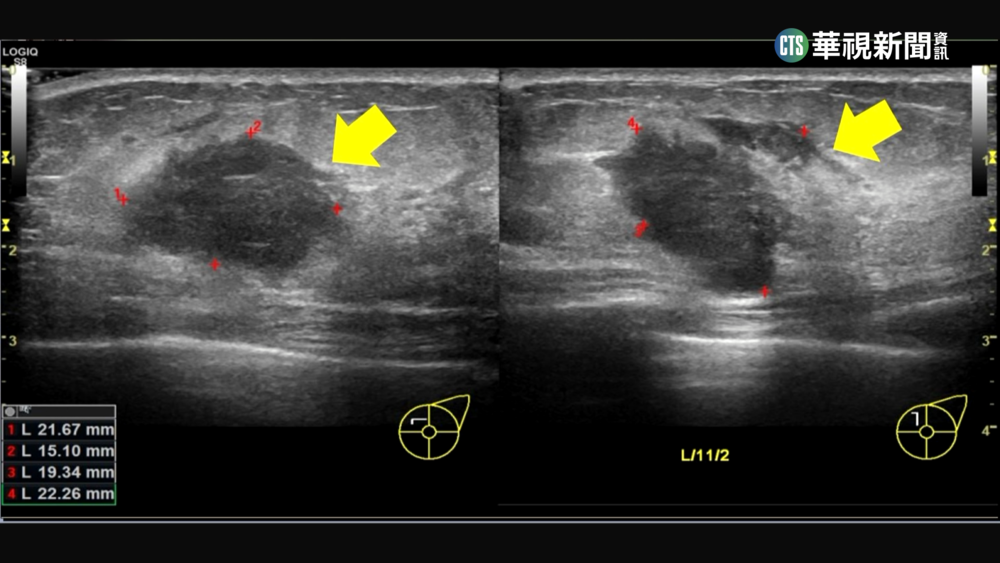

- 女檢出良性纖維腺瘤 怕染疫隔2年追蹤已乳癌2期2022/10/08